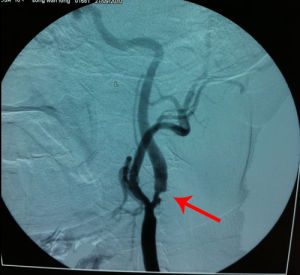

4.數字減影血管造影

目前雖然非創傷性影像學手段已越來越廣泛地套用頸部動脈病變的診斷,但每種方法都有肯定的優缺點。高解析度的MRA、CTA、都卜勒-超聲成像對初診、隨訪等具有重要的價值。雖然血管造影不再是普查、初診和隨訪的方法,但在精確評價病變和確定治療方案上,數字減影血管造影(digitalsubtractionangiography,DSA)仍是診斷頸動脈狹窄的“金標準”。頸動脈狹窄的DSA檢查應包括主動脈弓造影、雙側頸總動脈選擇性造影、顱內段頸動脈選擇性造影、雙側的椎動脈選擇性造影及基底動脈選擇性造影。

DSA可以詳細地了解病變的部位、範圍和程度以及側支形成情況;幫助確定病變的性質如潰瘍、鈣化病變和血栓形成等;了解並存血管病變如動脈瘤、血管畸形等。動脈造影能為手術和介入治療提供最有價值的影像學依據。動脈造影為創傷性檢查手段,且費用昂貴,文獻報導有0.3%~7%併發症的發生率。主要的併發症有腦血管痙攣、斑塊的脫落造成腦卒中、腦栓塞和造影劑過敏。腎功能損害、血管損傷及穿刺部位血腫、假性動脈瘤等。

儘管超聲、計算機X射線斷層成像(computerizedtomography,CT)、磁共振成像(magneticresonanceimaging,MRI)等無創性檢查在頸動脈狹窄診斷中的作用日益提高,但目前動脈造影仍是診斷頸動脈狹窄的“金標準”。頸動脈狹窄程度的判定依據動脈造影結果。